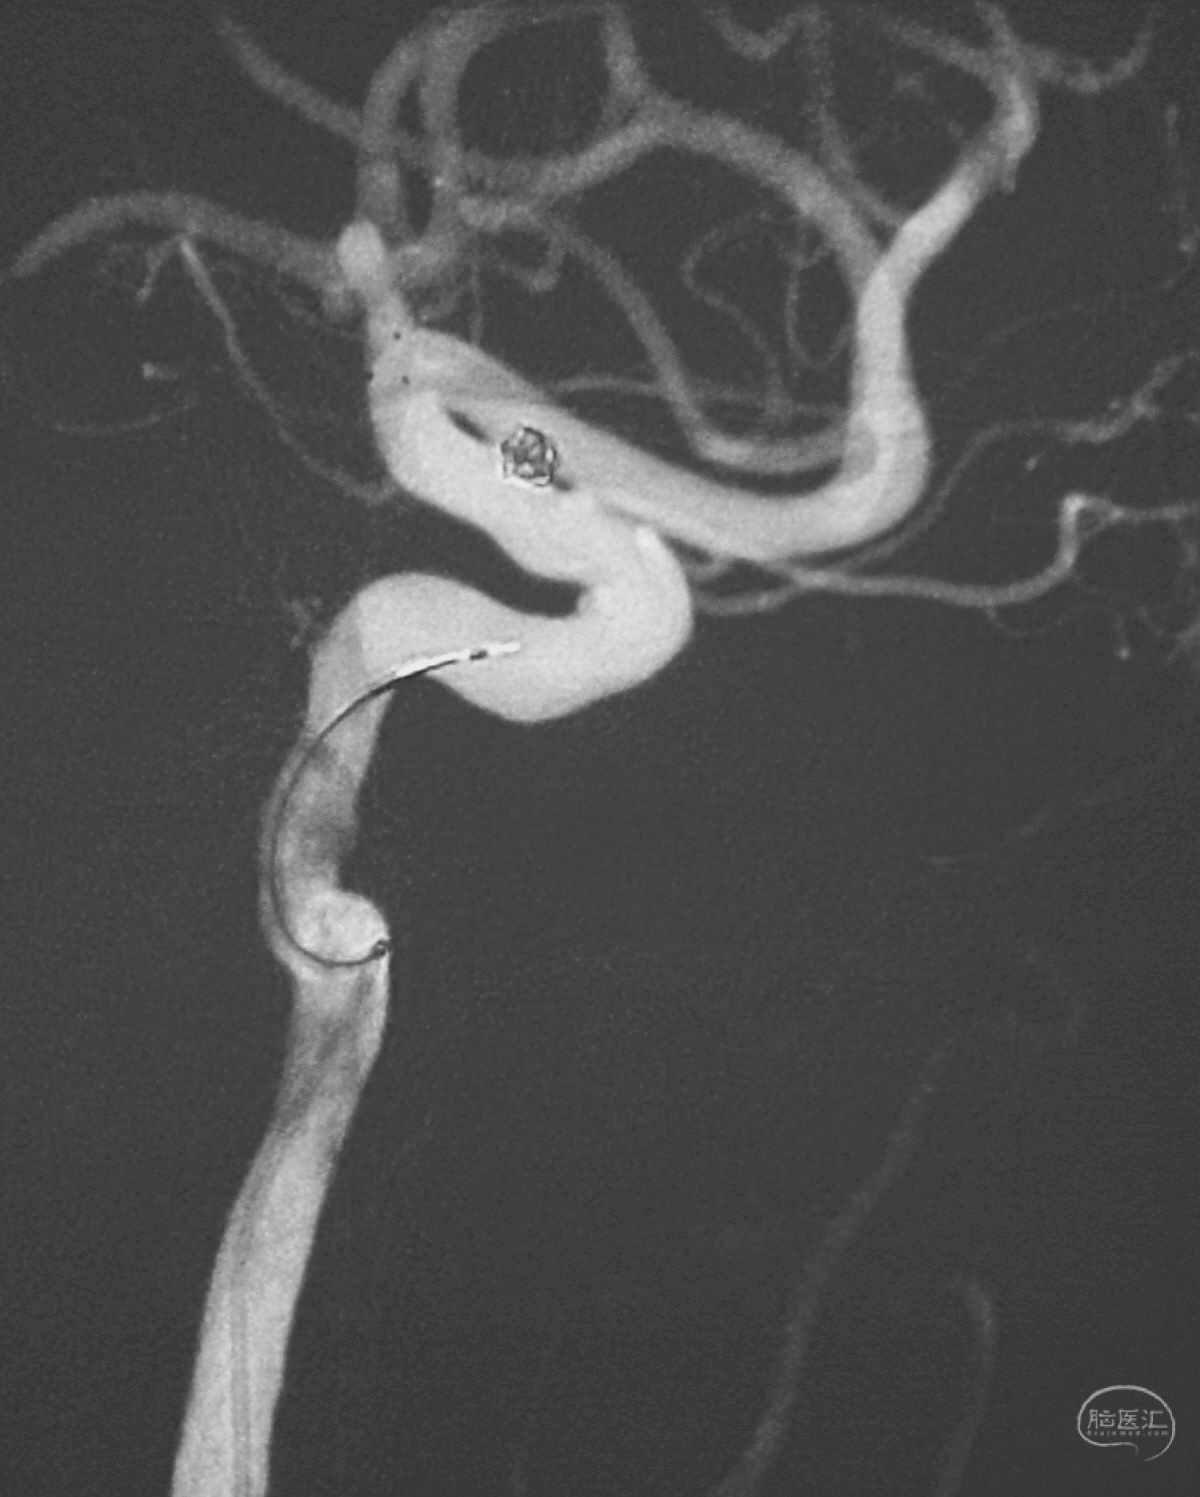

术后右椎动脉工作位造影,

以及正位造影显示动脉瘤完全栓塞,载瘤动脉畅通。